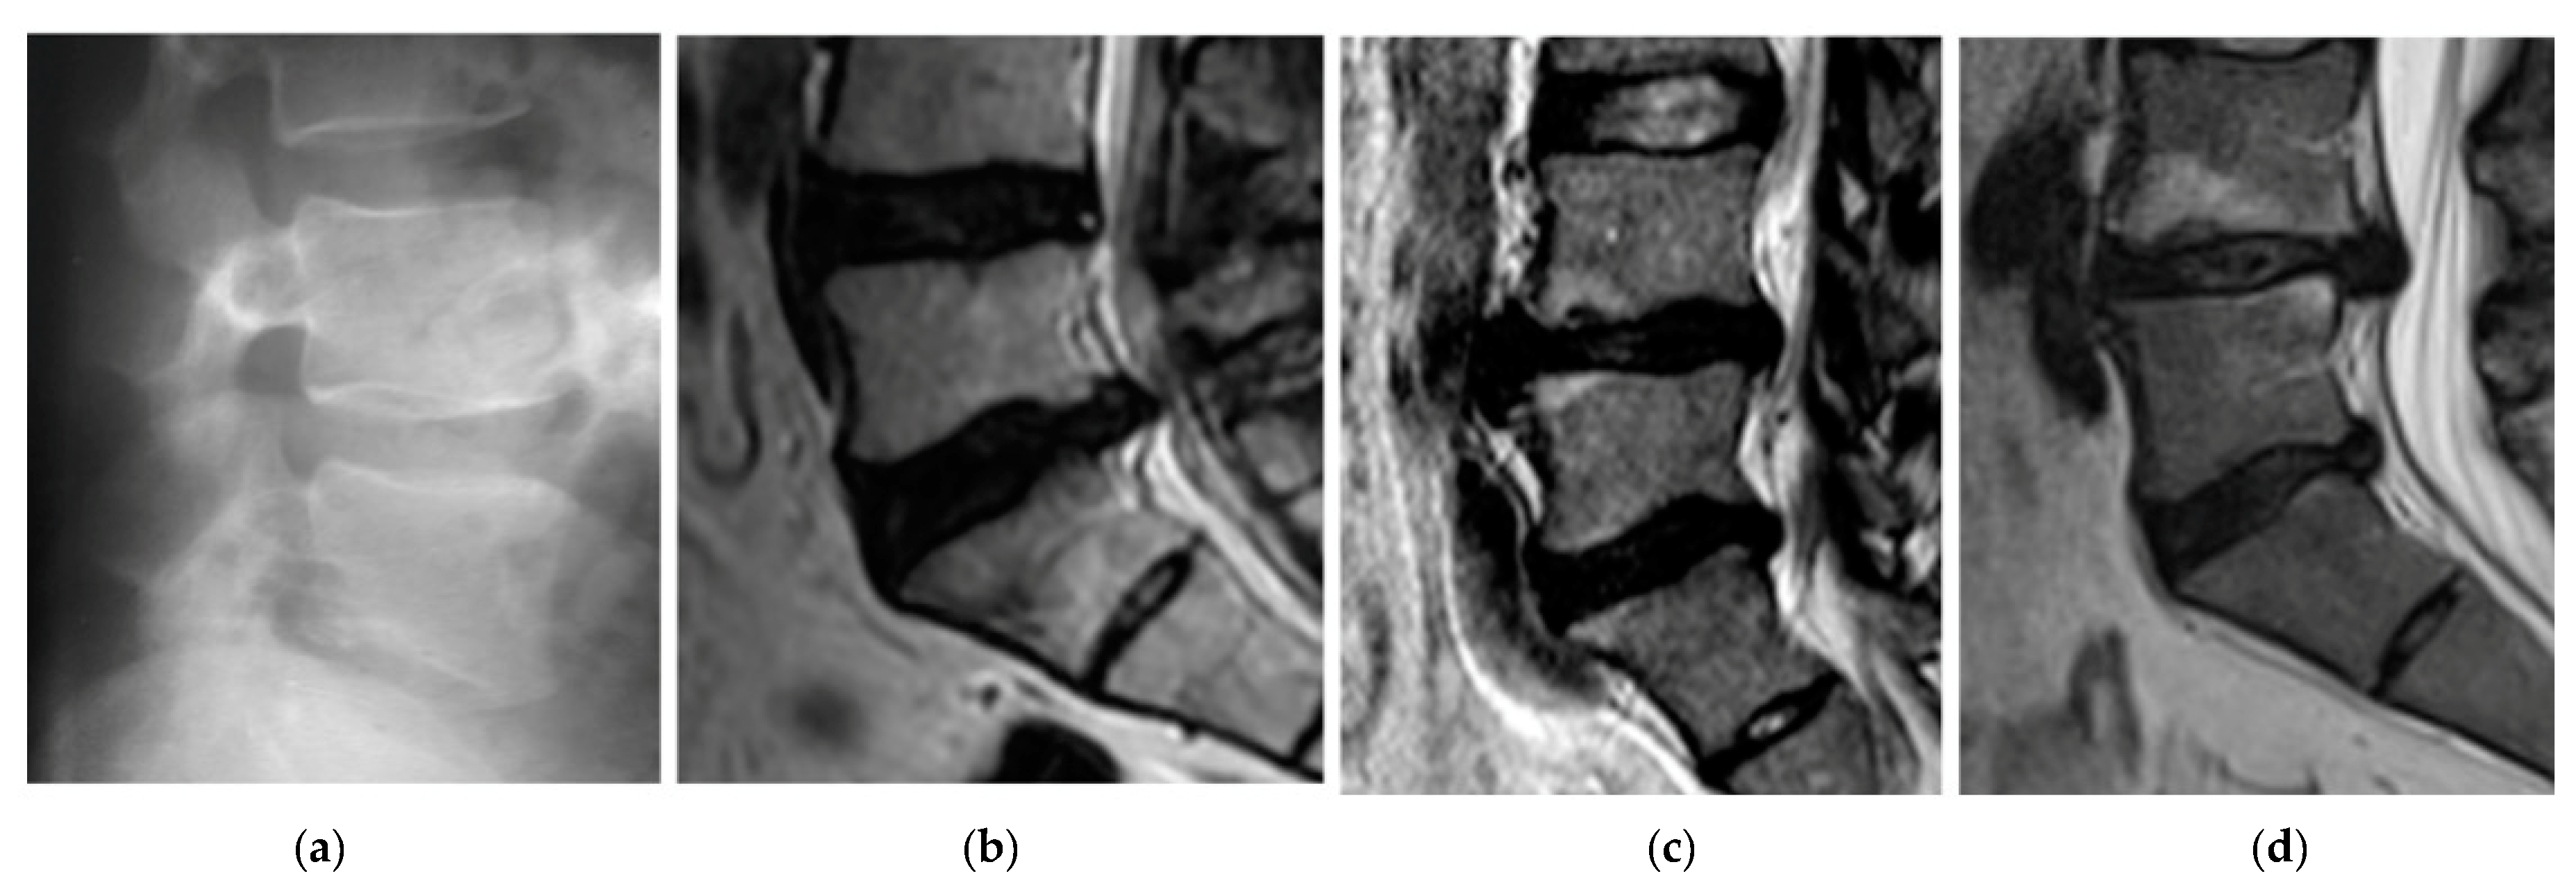

The first patient, A, was 44 years old, 1.76 m tall, and weighed 74 kg, meaning they were healthy (BMI 23.62). Diagnosis of the X-ray of the spine showed abolished physiological lumbar lordosis, a tendency to form kyphosis. The height of vertebral bodies and discs is preserved (Figure 3a). Patient A regularly engages in sports.

The second patient, B, was 46 years old, 1.77 m tall, and weighed 77 kg (BMI 24.58). The patient B has been leading a lifestyle for 10 years in which he does not play sports. He spends about 8 h a day at the computer. He complained of thigh and calf pain in the back of the limb from the 1 year. A study of MR spine, lumbosacral can be seen in Figure 3b. Other symptoms were dehydration of the intervertebral disc L5-S1, left-sided dislocation of the atherogenic nucleus to 6 mm, and the side bet filling with root pressure. Patient B participated in physiotherapy treatments and subjected to massages with without improvement. In the pharmacological treatment (in the severity of pain symptoms), patient B uses Skudexa (Tramadoli hydrochloridum 75 mg + Dexketoprofenum 25 mg) 1–2 times per month.

The third patient, C, was 42 years old, 1.75 m tall, and weighed 72 kg (BMI 23.51). He complained of paralysis of the left foot limb. A study of MR spine lumbosacral showed the smoothing lumbar lordosis and multilevel changes distorting the intervertebral joints. The symptoms of degenerative disc disease L4/L5/S1 with central protrusion disc m-k (it means “m-k”) L5/S1 entailing root compression, and the centre-left-sided disc protrusion m-k L4/L5 adjacent to the left L5 nerve root in the spinal canal were determined. The conclusion was the symptoms of lumbar disc L4/L5/S1, more the left body side at L4-L5 (Figure 3c). The disc herniation caused stretching and inflammation of an overlying nerve root. It also caused the leg pain, numbness, and tingling and weakness in the distribution of the nerve root.

The fourth patient, D, was 38 years old, 1.77 m tall, and weighed 70 kg (BMI 22.34). He complained of paralysis of the left foot limb (Figure 3d). A study of MR spine lumbosacral (2015.08.14) showed reduced intervertebral discs L4/L5, L5/S1, with reduction of their hydration, and bilateral narrowed intervertebral foramina L4/L5, L5/S1. At L4/L5 level, the central-right-side protrusion of the intervertebral disc is about 6.5 mm intrathecally with the impression of the right nerve root. At the L5/S1 level, the central-left lateral protrusion of the intervertebral disc is about 6 mm intrathecally and to the left lateral collateral. Due to severe pain and falling, foot surgery was performed on 2015/09/04. The herniation of the nucleus pulposus at the lumbar level was removed and the spinal canal was decompressed. Synthetic intervertebral baskets, struts, and threaded bone pins were introduced. Discectomy L4-L5 et stabilisatio intervertebralis posteriori columnae vertebralis eiusdem regionis BULLET TIP/2 × 9 mm × 26 mm, 1 × 10 mm × 26 mm/per fenestration protractam dextram.

Figure 3. Sagittal plane magnetic resonance imaging (MRI) cases: A—case (a) B—case (b) C—case (c) D—case (before surgery) (d).